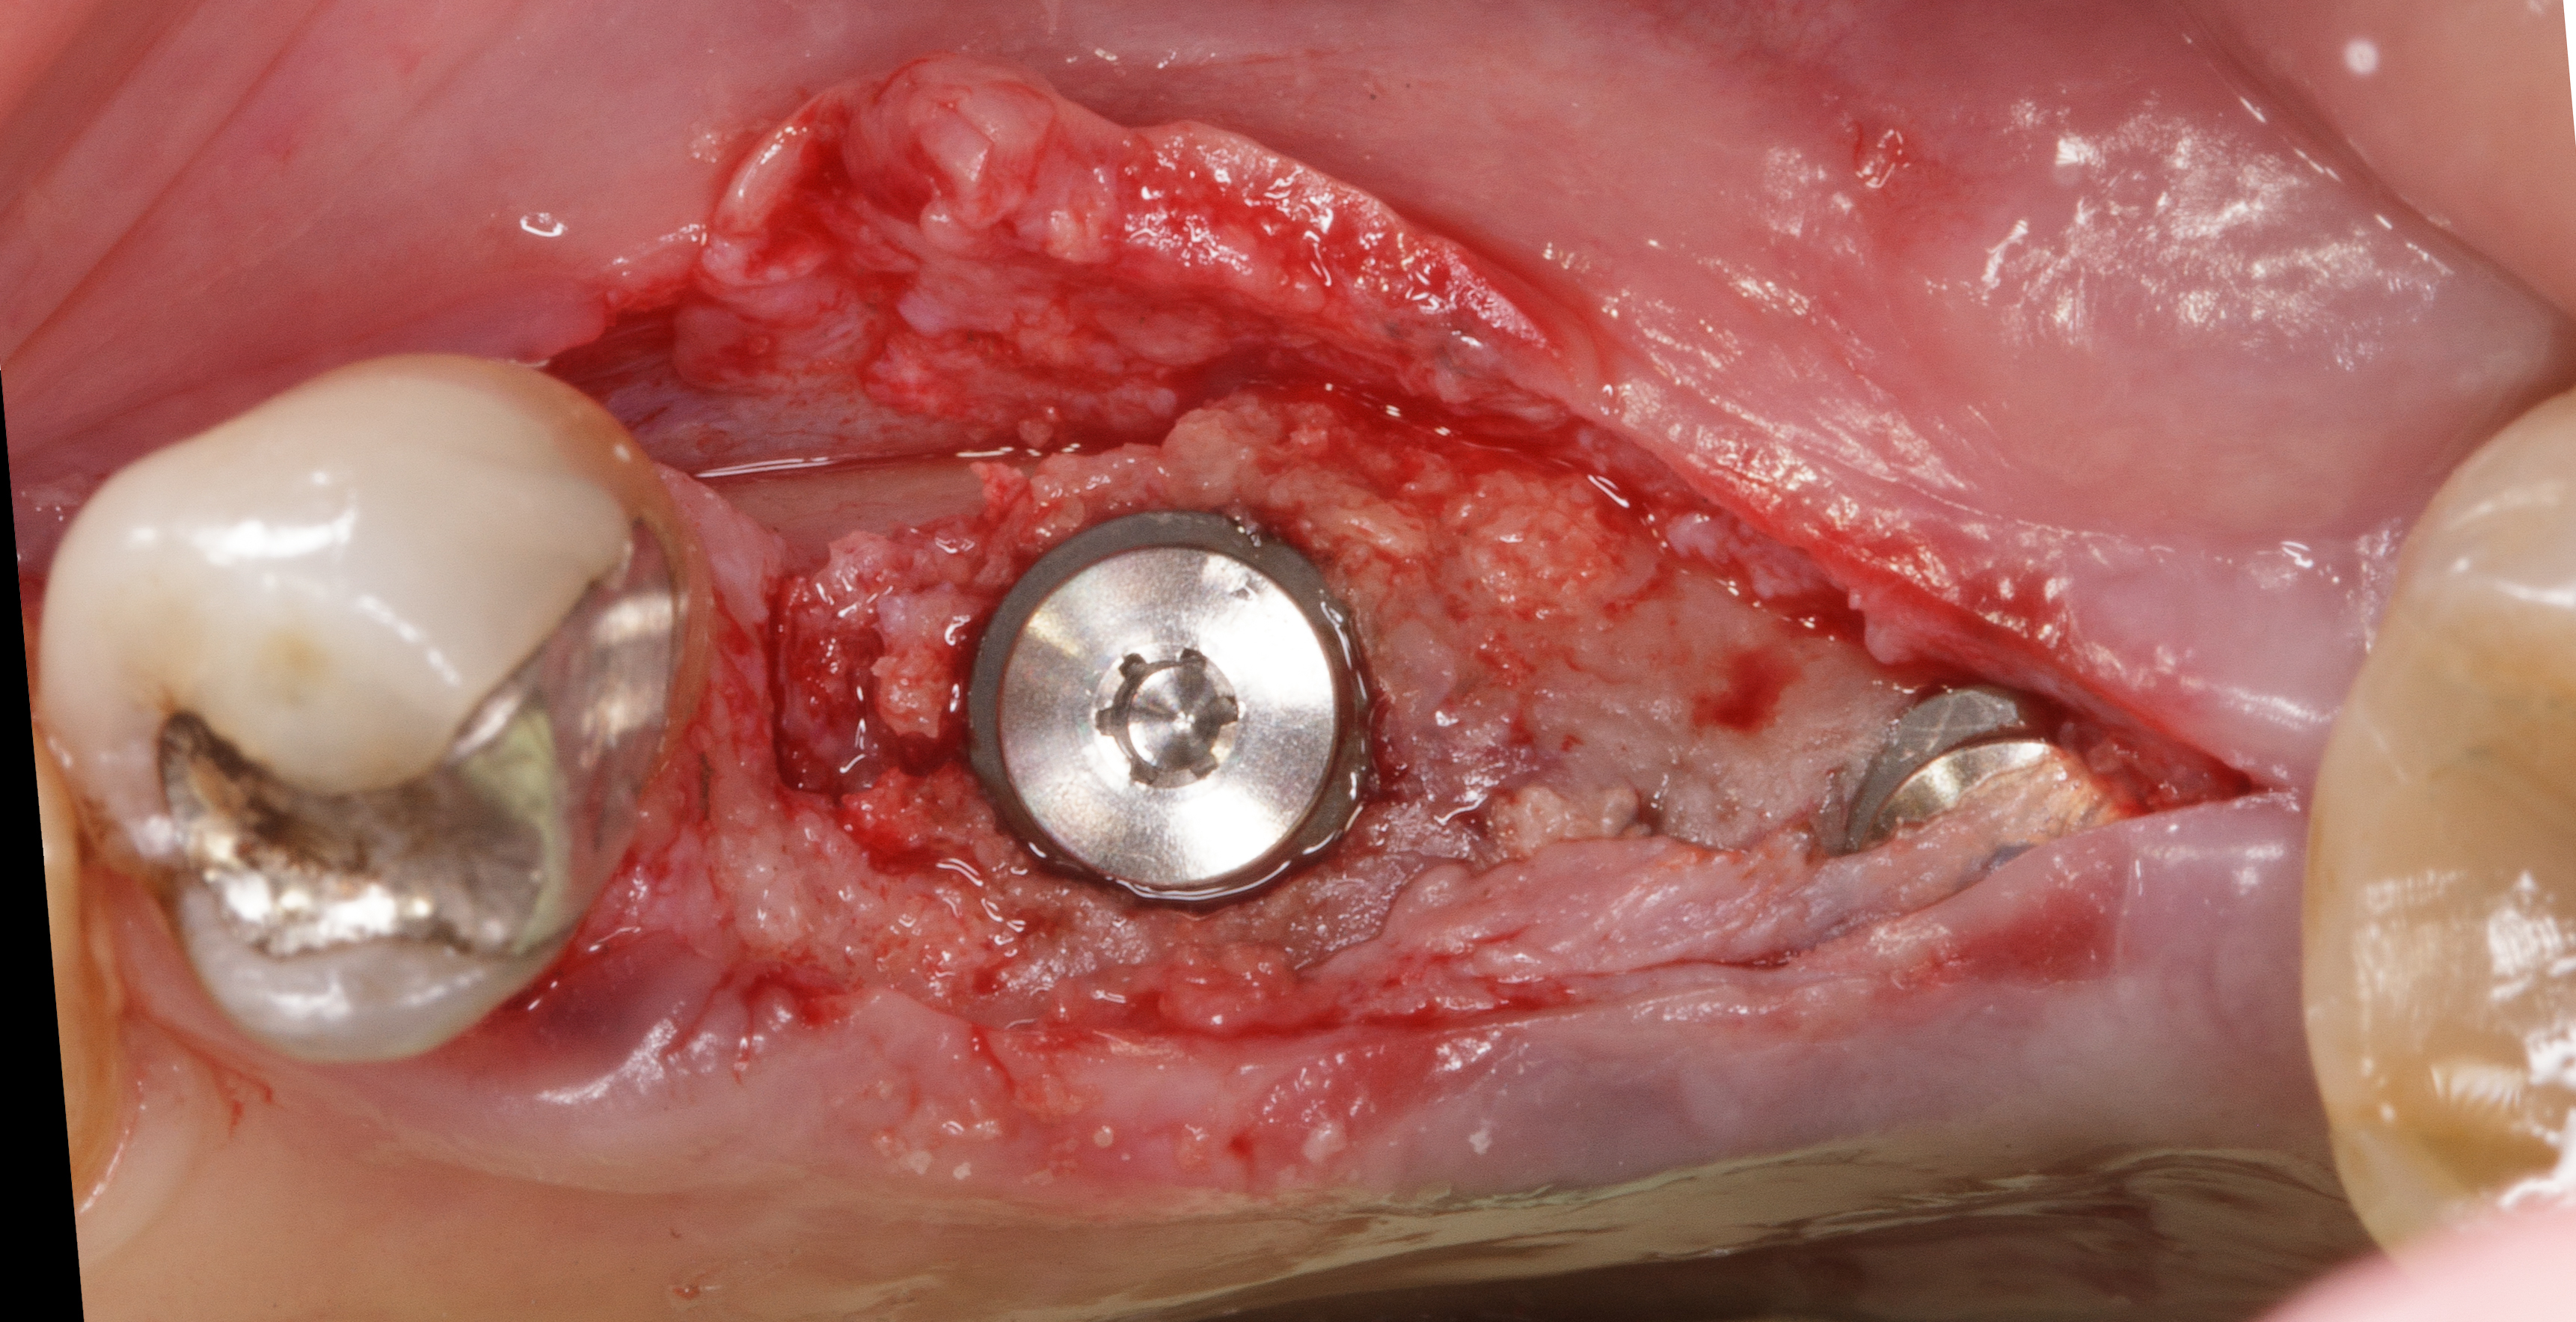

Dopo sei mesi dall’intervento di preservazione alveolare si inserisce un impianto differito in posizione 4.5.

Dopo esecuzione di lembo mucoperiosteo con una incisione di prolungamento mesiale a preservazione papillare, si osserva la presenza di tessuto osseo compatto in posizione premolare.

La corticale vestibolare e crestale non è ancora completamente formata, ma la visione in senso occlusale mostra come il tessuto osseo, che è ancora in fase di mineralizzazione, sia oltre il limite del bone housing dell’alveolo originario.

Si è ottenuta una preservazione del volume osseo oltre il 100% (Figure 18-19).